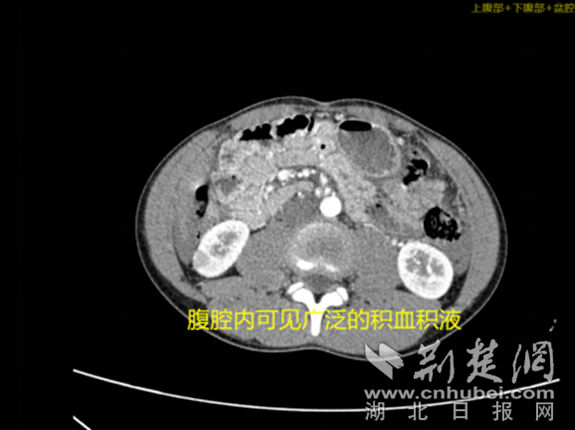

经过询问,涛涛告诉医生,两辆自行车相撞时,他的右上腹部被对方的自行车把手顶到过,还在隐隐作痛。出于专业敏感性,医生迅速给涛涛完善了胸腹部的增强CT,然而这一检查却让家属惊出一身冷汗。检查结果显示,涛涛肝脏破裂并腹腔积液、积血,如果肝部动脉出血不能控制,孩子可能因为失血性休克而危及生命,手术是首选治疗方案。

腹腔内可见广泛的积血积液 通讯员 供图